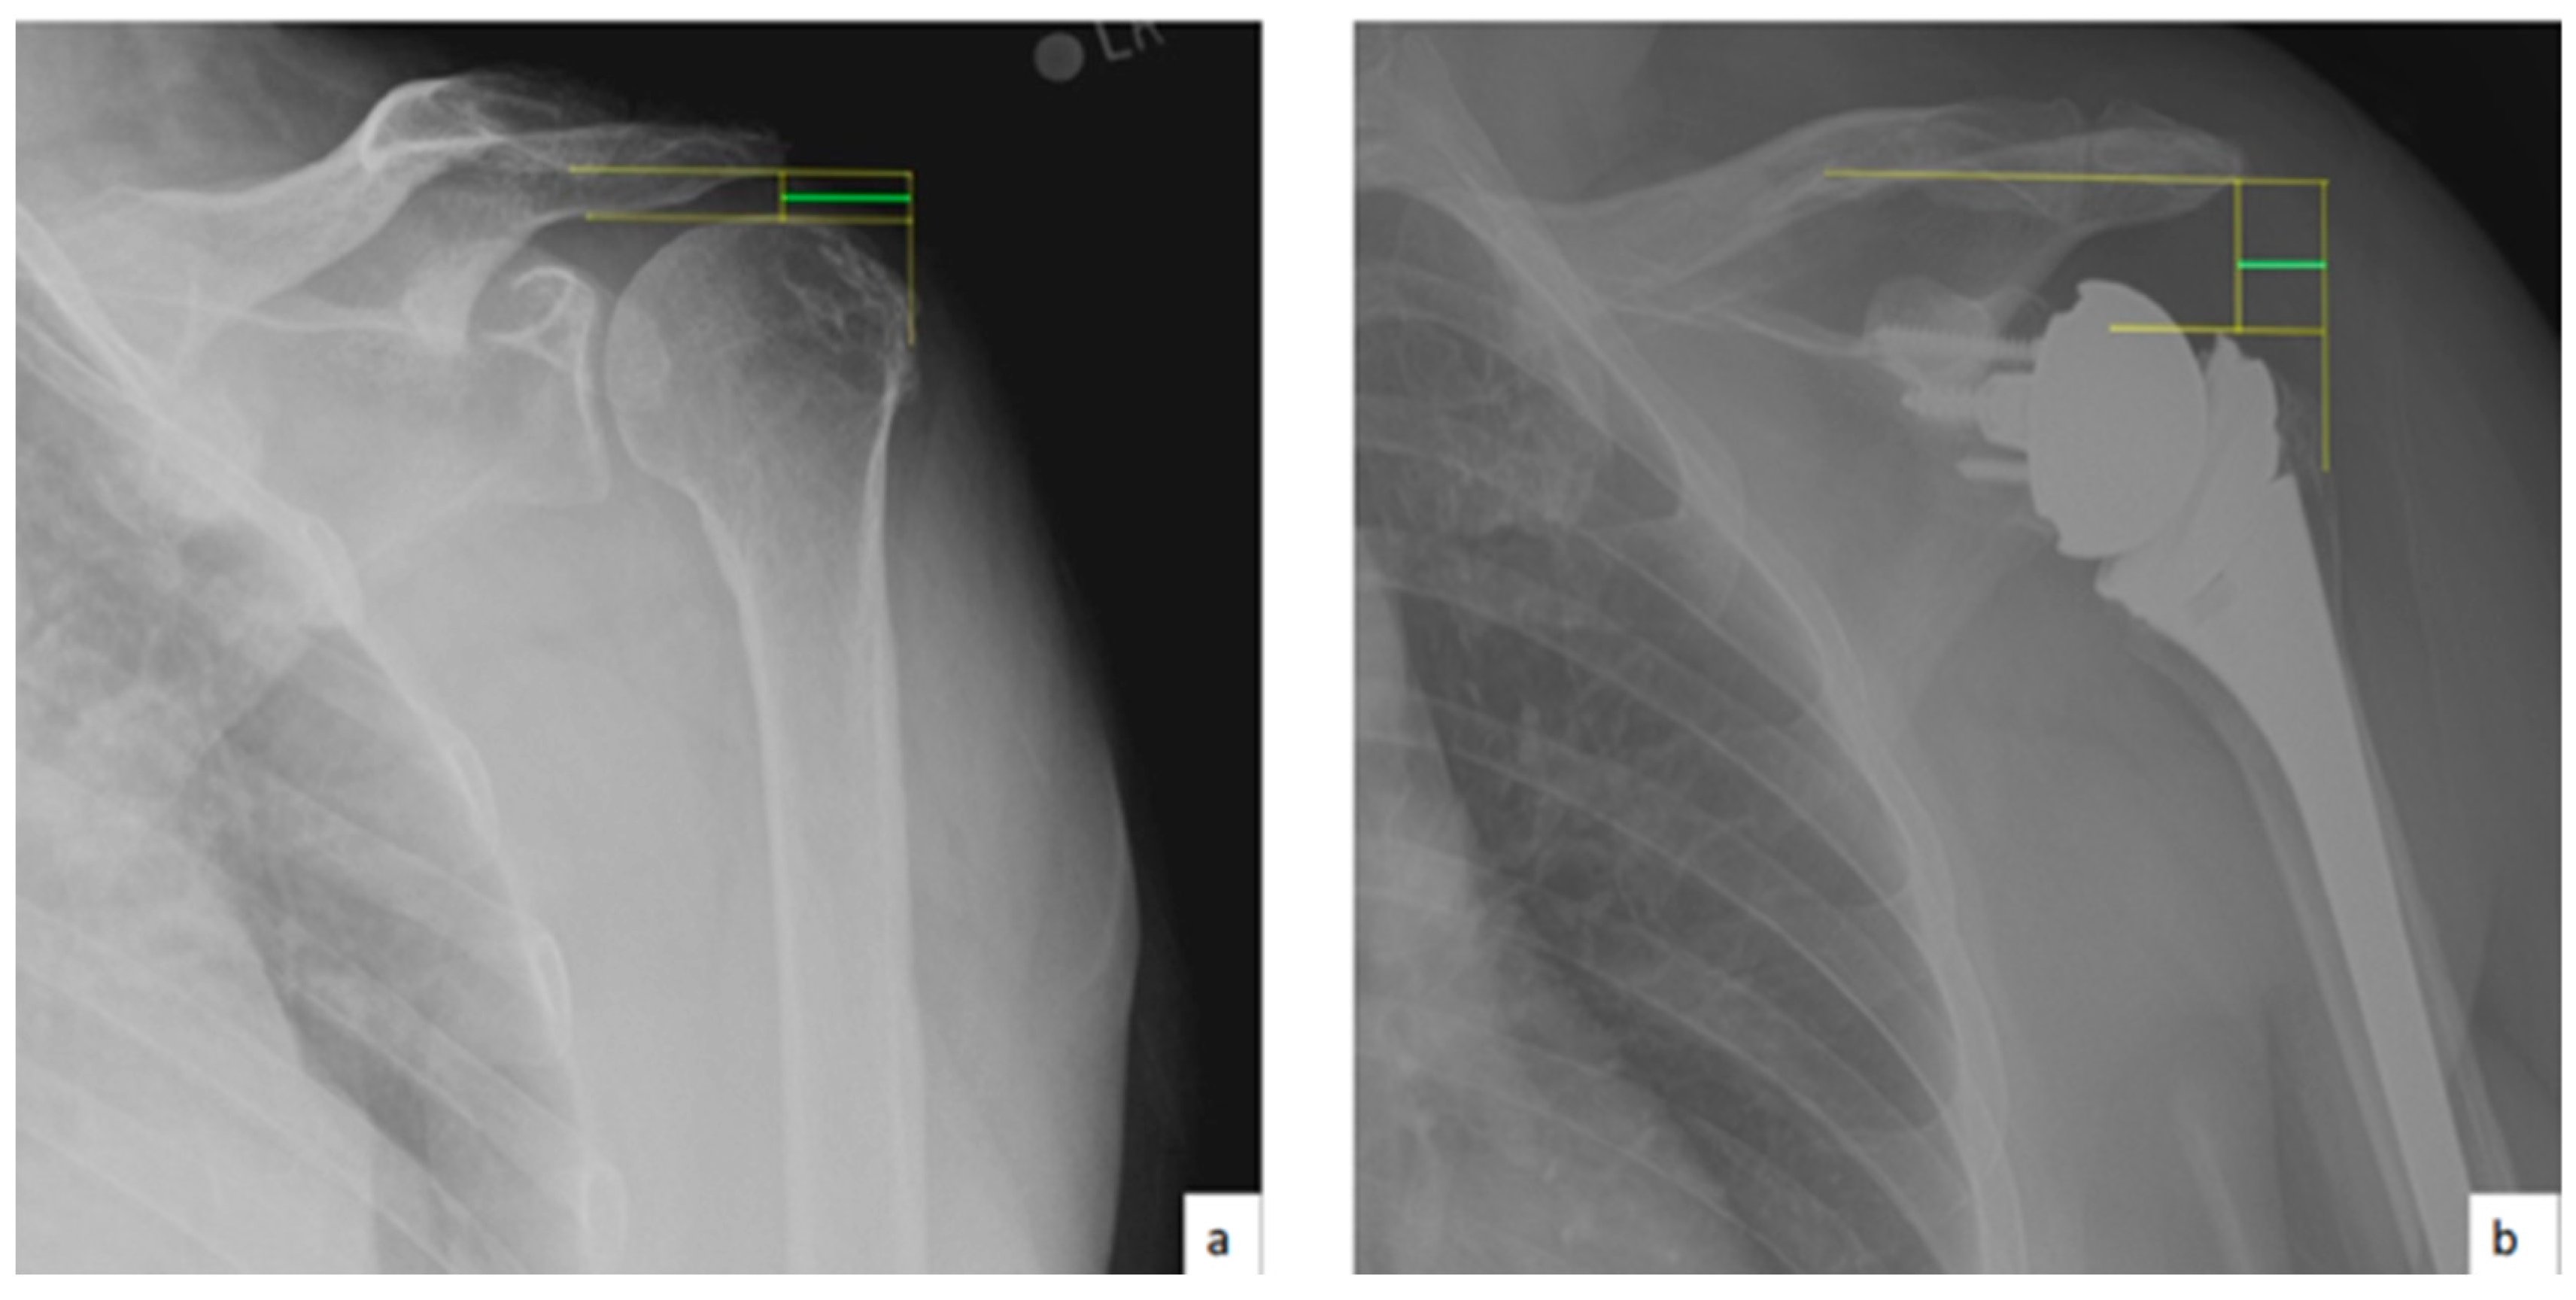

AHD was measured by calculating the perpendicular distance between the most lateral portion of the undersurface of the acromion and a line parallel to the superior border of the greater tuberosity [21] (Figure 1). LHO was measured by determining the distance from the AHD line to the most lateral projection of the greater tuberosity [21] (Figure 2). LSA was measured by drawing a line from the superior glenoid tubercle to the most lateral border of the acromion and a second line from the most lateral border of the acromion to the most lateral border of the greater tuberosity. The angle between these two lines formed the LSA [20] (Figure 3a). DSA was measured by drawing a line between the most lateral border of the acromion and the superior glenoid tubercle and drawing a second line to connect the superior glenoid tubercle with the most superior border of the greater tuberosity. The angle between these two lines formed the DSA [20] (Figure 3b). Glenoid and baseplate were determined as the angle between the floor of the supraspinatus fossa and the glenoid fossa [25] (Figure 4). COR was measured by determining the best fit circle flush to the articular surface, identifying the center of the circle in the humeral head, and then measuring the distance of the perpendicular line between the center of the humeral head and the midpoint of the line connecting the superior and inferior glenoid tubercles [24] (Figure 5b). CSA was measured by a line from the superior pole to the inferior pole of the glenoid and a line from the inferior pole to the lateral edge of the acromion [26] (Figure 5a). In addition, scapular notching was graded according to the Nerot–Sirveaux classification and severity of preoperative cuff tear arthropathy was evaluated according to the Hamada classification [27,28].

Figure 2.

(a) Preoperative lateral humeral offset (LHO; green line); (b) postoperative lateral humeral offset (LHO; green line).